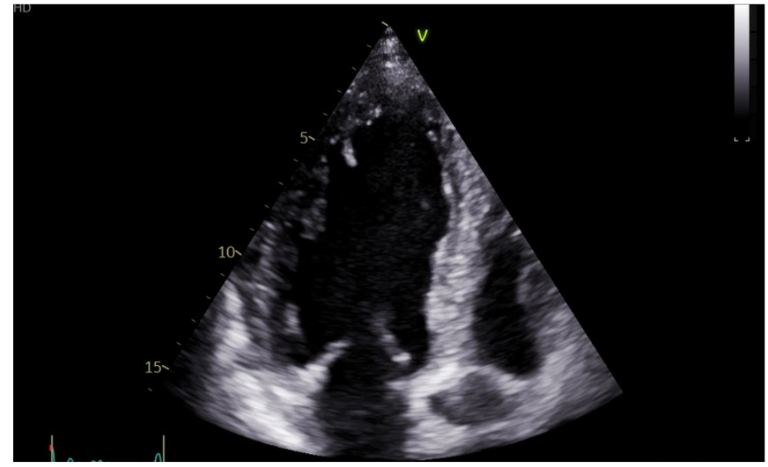

Ingresa a hospitalización y se toman los paraclínicos, los cuales reportan: péptido natriurético tipo B (NT PROBNP): muy elevado de 66.526, electrocardiograma (ECG) con ritmo sinusal, eje desviado a la izquierda y sin trastorno de la repolarización del segmento ST; radiografía de tórax con opacidades en vidrio deslustrado, sin consolidaciones, cardiomegalia y derrame pleural bilateral (figura 1); ecocardiograma transtorácico (ECO TT), donde se evidencia una cardiopatía isquémica con hipertrofia excéntrica del ventrículo izquierdo (VI) con alteraciones de la contractilidad y disfunción sistólica severa, una fracción de eyección del ventrículo izquierdo (FEVI) del 30 %, STRAIN global longitudinal de -7,3 %, disfunción diastólica moderada y una severa dilatación de la aurícula izquierda (AI); además de hipertensión pulmonar de PSAP de 49 mmHg (probabilidad intermedia), ventrículo derecho de tamaño y función normal (figura 2).